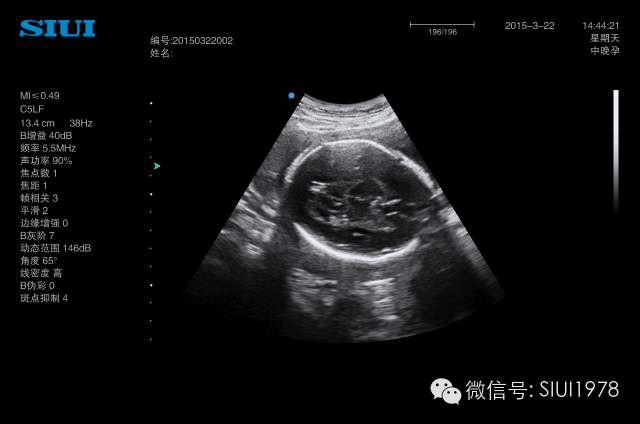

近年来超声医学的发展日新月异,彩色多普勒、三维超声、四维超声等新技术广泛应用。在妇产科领域,产前超声诊断的需求显著增加。由于兼有无创、便捷、价廉、实时、动态等优点,超声检查已成为目前临床上筛查胎儿发育畸形中最常用的影像学手段。

近年来,颜面部结构的辨认与颜面部畸形的产前超声诊断越来越受到人们的重视,三维超声的飞速发展,能将颜面部结构及畸形非常逼真地展现在人们面前。随着超声仪器的不断发展,图像分辨力的不断提高,颜面部的许多细小结构及某些面部表情亦能清晰可辨,如胎儿人中的显示,胎儿争眼、皱额等细微表情动作的显示与观察等。眼眶、眼球、眼裂、眼睑、前额、鼻、鼻骨、上下唇、人中、上颌骨及上牙槽突与其内的牙胚、下颌骨及下牙槽突与其内的牙胚、下颌、硬腭、舌、口、颧骨、耳廊等结构均能清晰可辨,因此,对这些正常结构的正确认识,对提高颜面部结构畸形的认识是非常有帮助的。

一、 胎儿正常颜面部的超声解剖